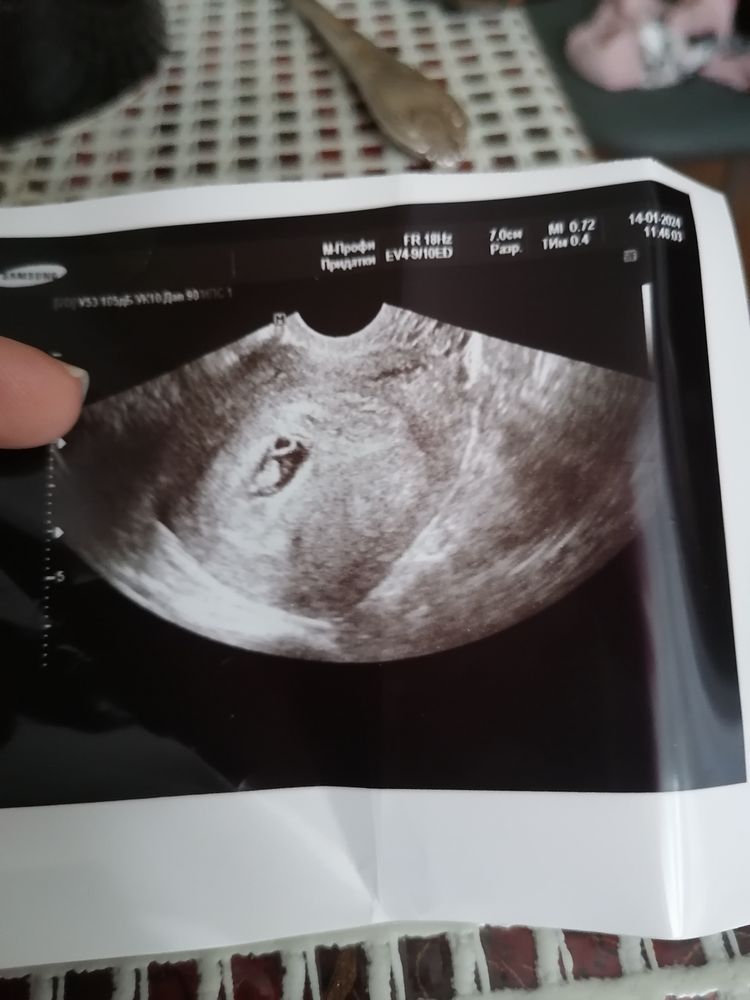

Всем здравствуйте, сегодня была на УЗИ срок все так же на неделю ровно по месячным меньше, но доктор сказала что с твоим циклом все нормально ориентируемся по узи, а не по месячным. Сделали фото, неделю назад уже было сердцебиение (+), сегодня тоже все сказали хорошо, но только фото дали в не чего не объяснили что где)) может кто разбирается что где??